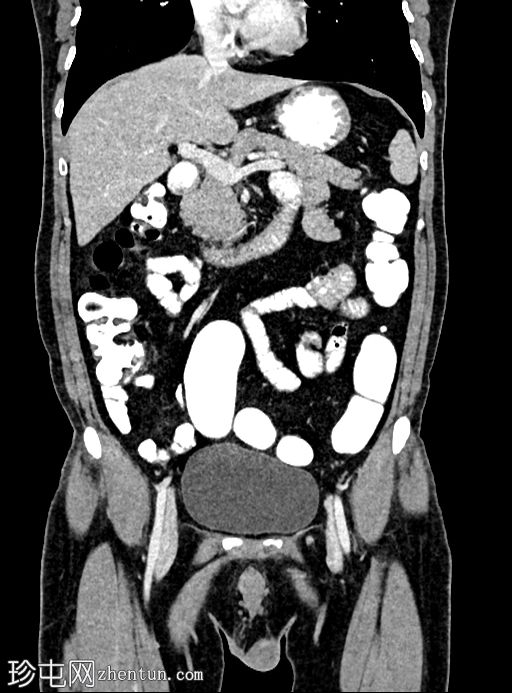

冠状位增强扫描

门静脉期

乙状结肠旁可见两处小的脂肪衰减病灶。较小的病灶呈周边环状强化,伴有轻度邻近脂肪条索状改变 → 急性大网膜垂炎。

较大的病灶呈薄环状强化,周围无炎症 → 消退期/慢

性病

变。未见肠壁增厚,未见肠腔相通,无游离液体或积液。

大网膜垂炎是指由于扭转或静脉血栓形成引起的大网膜垂缺血性炎症,最常见于乙状结肠旁。 CT

影像

具有特征性,有助于避免不必要的抗生素或手术。